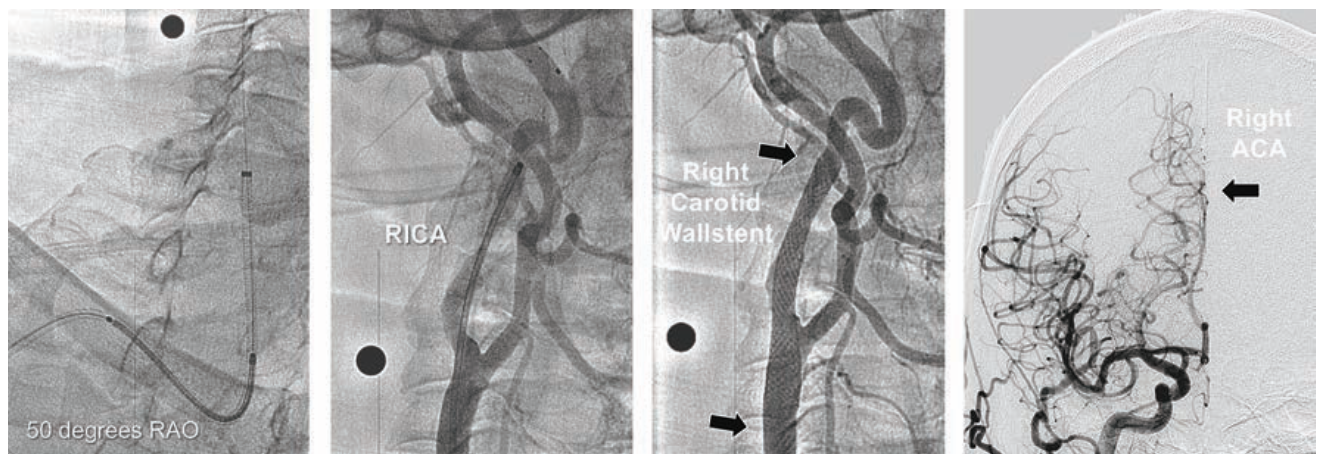

Case #8

A 72-year-old female with progressive asymptomatic >80% right carotid stenosis on carotid duplex ultrasound, status post right lung lobectomy with severe oxygen-dependent lung disease, was referred for carotid stenting. Using right 5 Fr TRA, a thoracic aortic arch angiogram was performed. A 5 Fr Simmons-1 glide catheter (Cook Medical) was directed into the left carotid artery for imaging of left internal carotid and intracerebral circulation, revealing filling of both left and right anterior cerebral arteries (Figure 8A). The Simmons-1 catheter was redirected into the innominate artery, and then withdrawn in order to cannulate the right common carotid artery for imaging the right internal carotid artery stenosis, and intracerebral circulation. Prior to carotid stenting, the right anterior cerebral artery did not fill by right carotid artery flow.

With the Simmons-1 catheter “secured” into the proximal common carotid artery, an .035-inch 260 cm angled Glidewire (Terumo) was advanced into the right external carotid artery. The radial access sheath was exchanged for a 5 Fr 90 cm Flexor Shuttle sheath, which was advanced into the right common carotid artery, with removal of the Glidewire. A 180 cm .014-inch hydrophilic coronary guidewire was used to cross the right internal carotid lesion, with exchange for a SpiderFX 7 mm capture filter wire. A 6 mm diameter metallic sphere positioned on the patient’s neck assisted in vessel sizing. Pre-dilatation was performed using an .014-inch Sterling Monorail RX 4 mm x 20 mm balloon on a 135 cm catheter (Boston Scientific). An. 014-inch carotid Wallstent 8 mm x 36 mm on a 135 cm monorail RX catheter (Boston Scientific) was deployed to cover the carotid lesion, positioned below the level of the acute bend in the right internal carotid artery. Postdilation was performed with a 5 mm x 20 mm Sterling RX balloon. Following filter retrieval, intracerebral angiography demonstrated restoration of antegrade flow into the right anterior cerebral artery (Figure 8B). After hemostasis with a TR Band, the patient ambulated immediately, and neurologic testing remained normal.

Tips and Tricks for 5 Fr Carotid Artery Stenting

Right carotid artery stenting using 5 Fr TRA may reduce the number of catheter manipulations required in diseased thoracic aortic arches as compared to femoral artery access. This could decrease risks for embolization during common carotid artery cannulation and guide sheath placement. The 5 Fr Shuttle sheath allowed excellent imaging when using the .014-inch monorail PTA balloons and .014-inch monorail Wallstent delivery system. For 5 Fr guide sheath delivery, carotid Wallstent technology is available in 6 and 8 cm diameters, with 21, 29, and 36 mm unconstrained lengths.